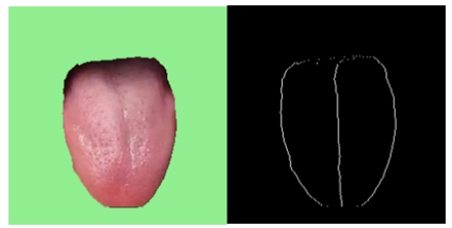

(1)用户上传的舌象图片已经被分割完成;

首先是要将舌象图片进行舌体分割(参照计算机视觉智能中医(三):基于Unet模型的舌头舌体图片分割)

舌体胖瘦分析的主要的对象是中下舌位,上舌位会影响分析的准确性,因此取舌体轮廓标记点的下0.75舌位。示意图如下图所示:

对下0.75舌位标记像素点进行舌体轮廓的多项式曲线拟合。由于分析的是曲线的“胖瘦”,因此多项式曲线的奇数次项影响较小,且项数较大较好。权衡模型的运行效率,中e诊采用4次项多项式曲线拟合。进行多张图片拟合的确定系数(R-square=SSR/SST)为0.82~0.95,说明4次多项式曲线拟合效果较好。舌体轮廓4次多项式拟合示意图如下: